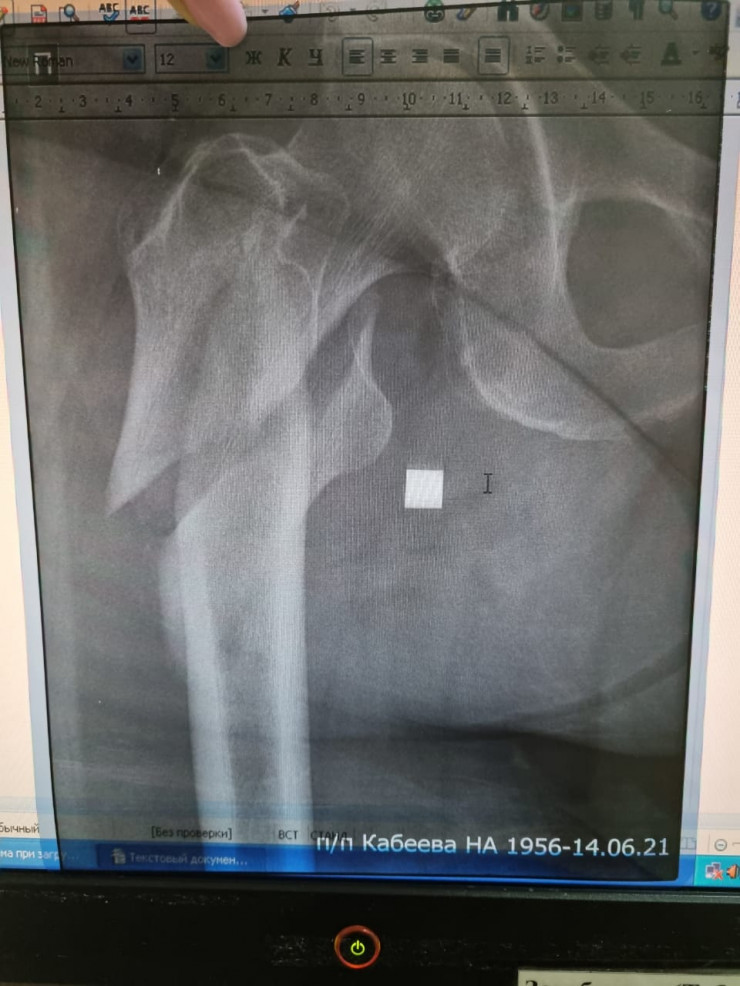

В аэропорту пенсионерке оказали первую медицинскую помощь - сделали укол обезболивающего и измерили давление. Позже женщину госпитализировали в областную больницу, у нее оказался перелом бедра. По словам дочери пострадавшей, ее маму ждут долгое лечение и реабилитация. Но администрация аэропорта решила, по ее словам, занять выжидательную позицию. В первые дни после инцидента они даже не поинтересовались здоровьем пенсионерки.

Фото предоставлены дочерью пострадавшей